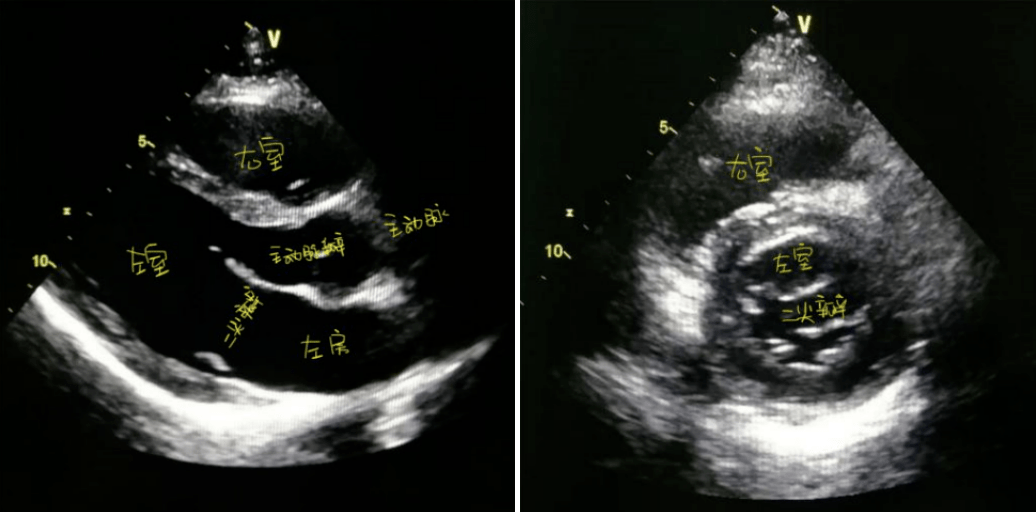

rv:右室;la:左房;m:二尖瓣;a:主动脉瓣(1)二尖瓣观察有无钙化,畸形

二尖瓣:正常瓣口面积 4~6 cm05.